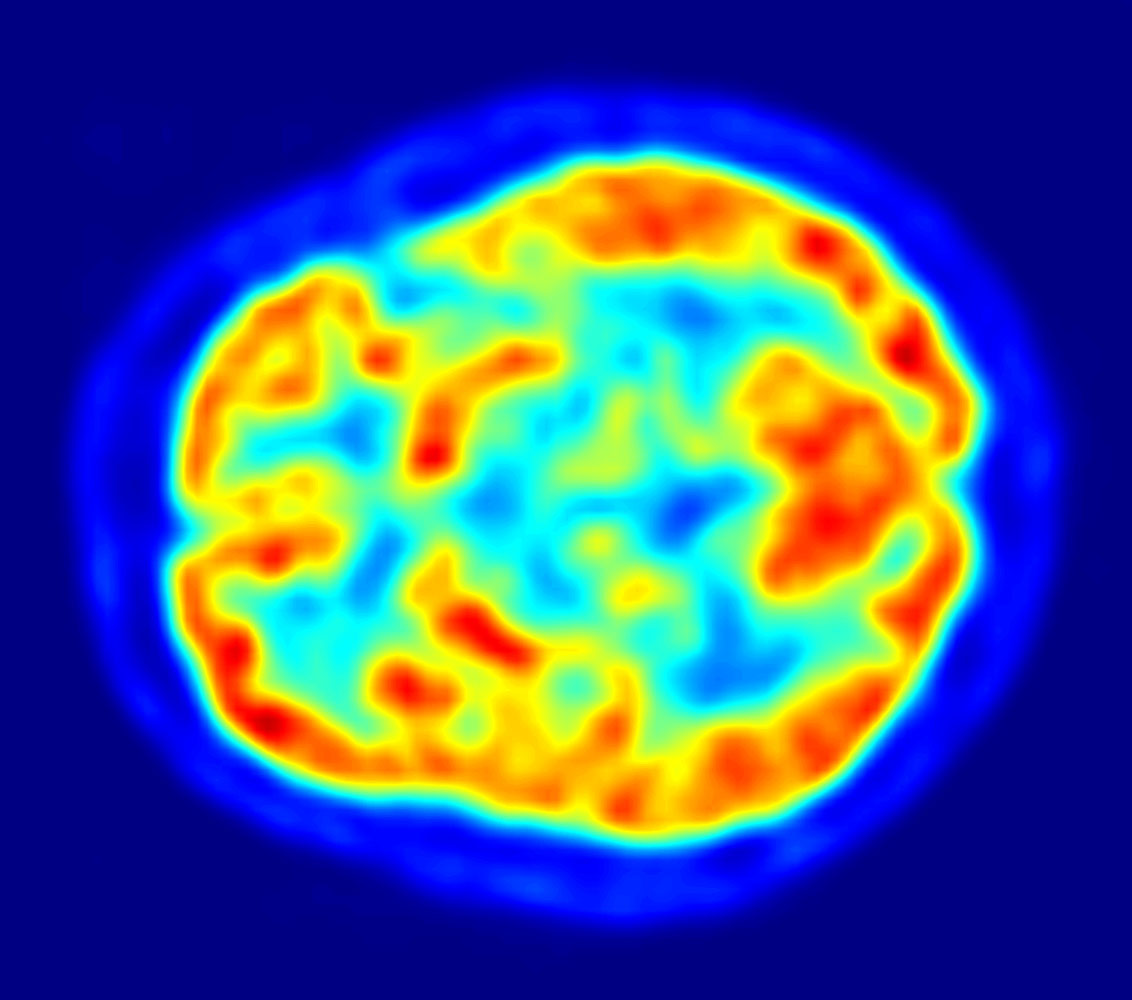

PET扫描图像:通过探测正电子湮灭产生的γ光子对,PET可以显示体内代谢活动的分布

- PET扫描图像示例:Wikimedia Commons - PET-image,Public Domain